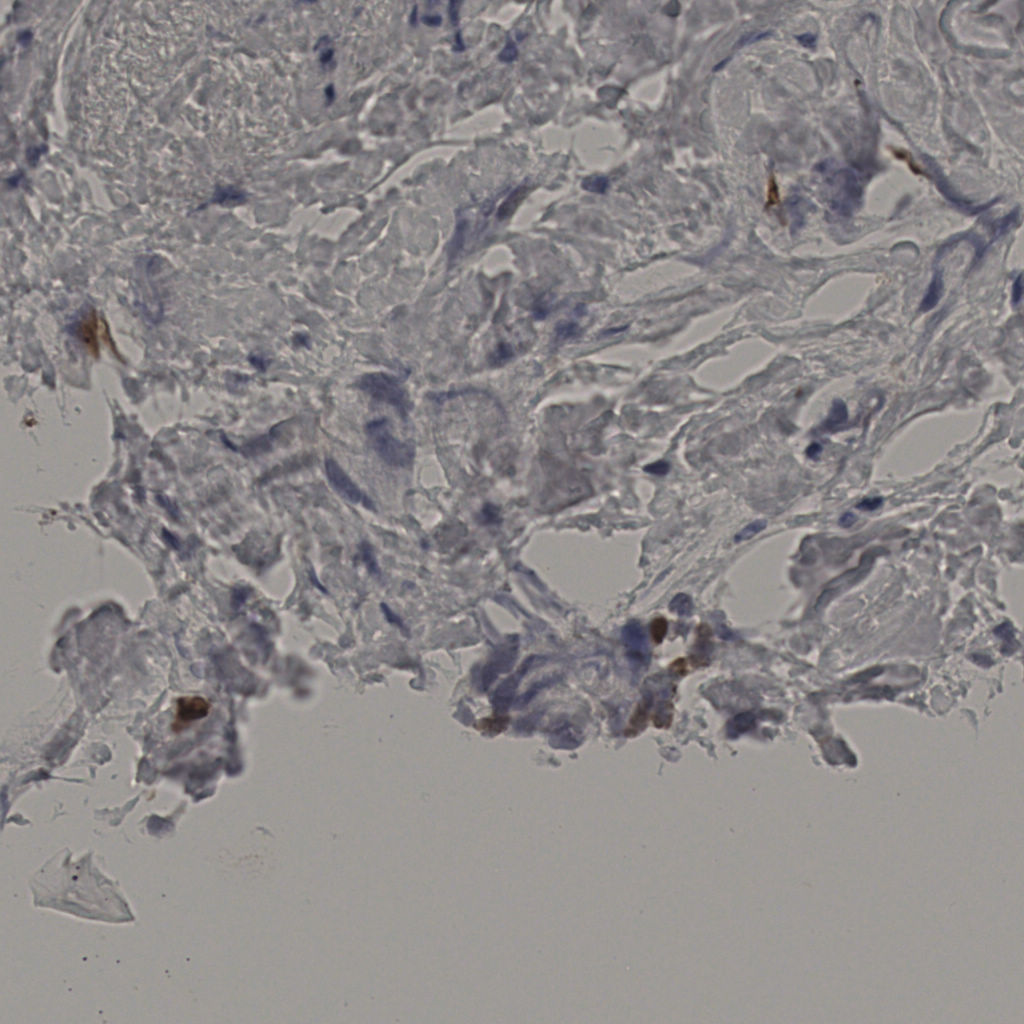

标记后

标记前